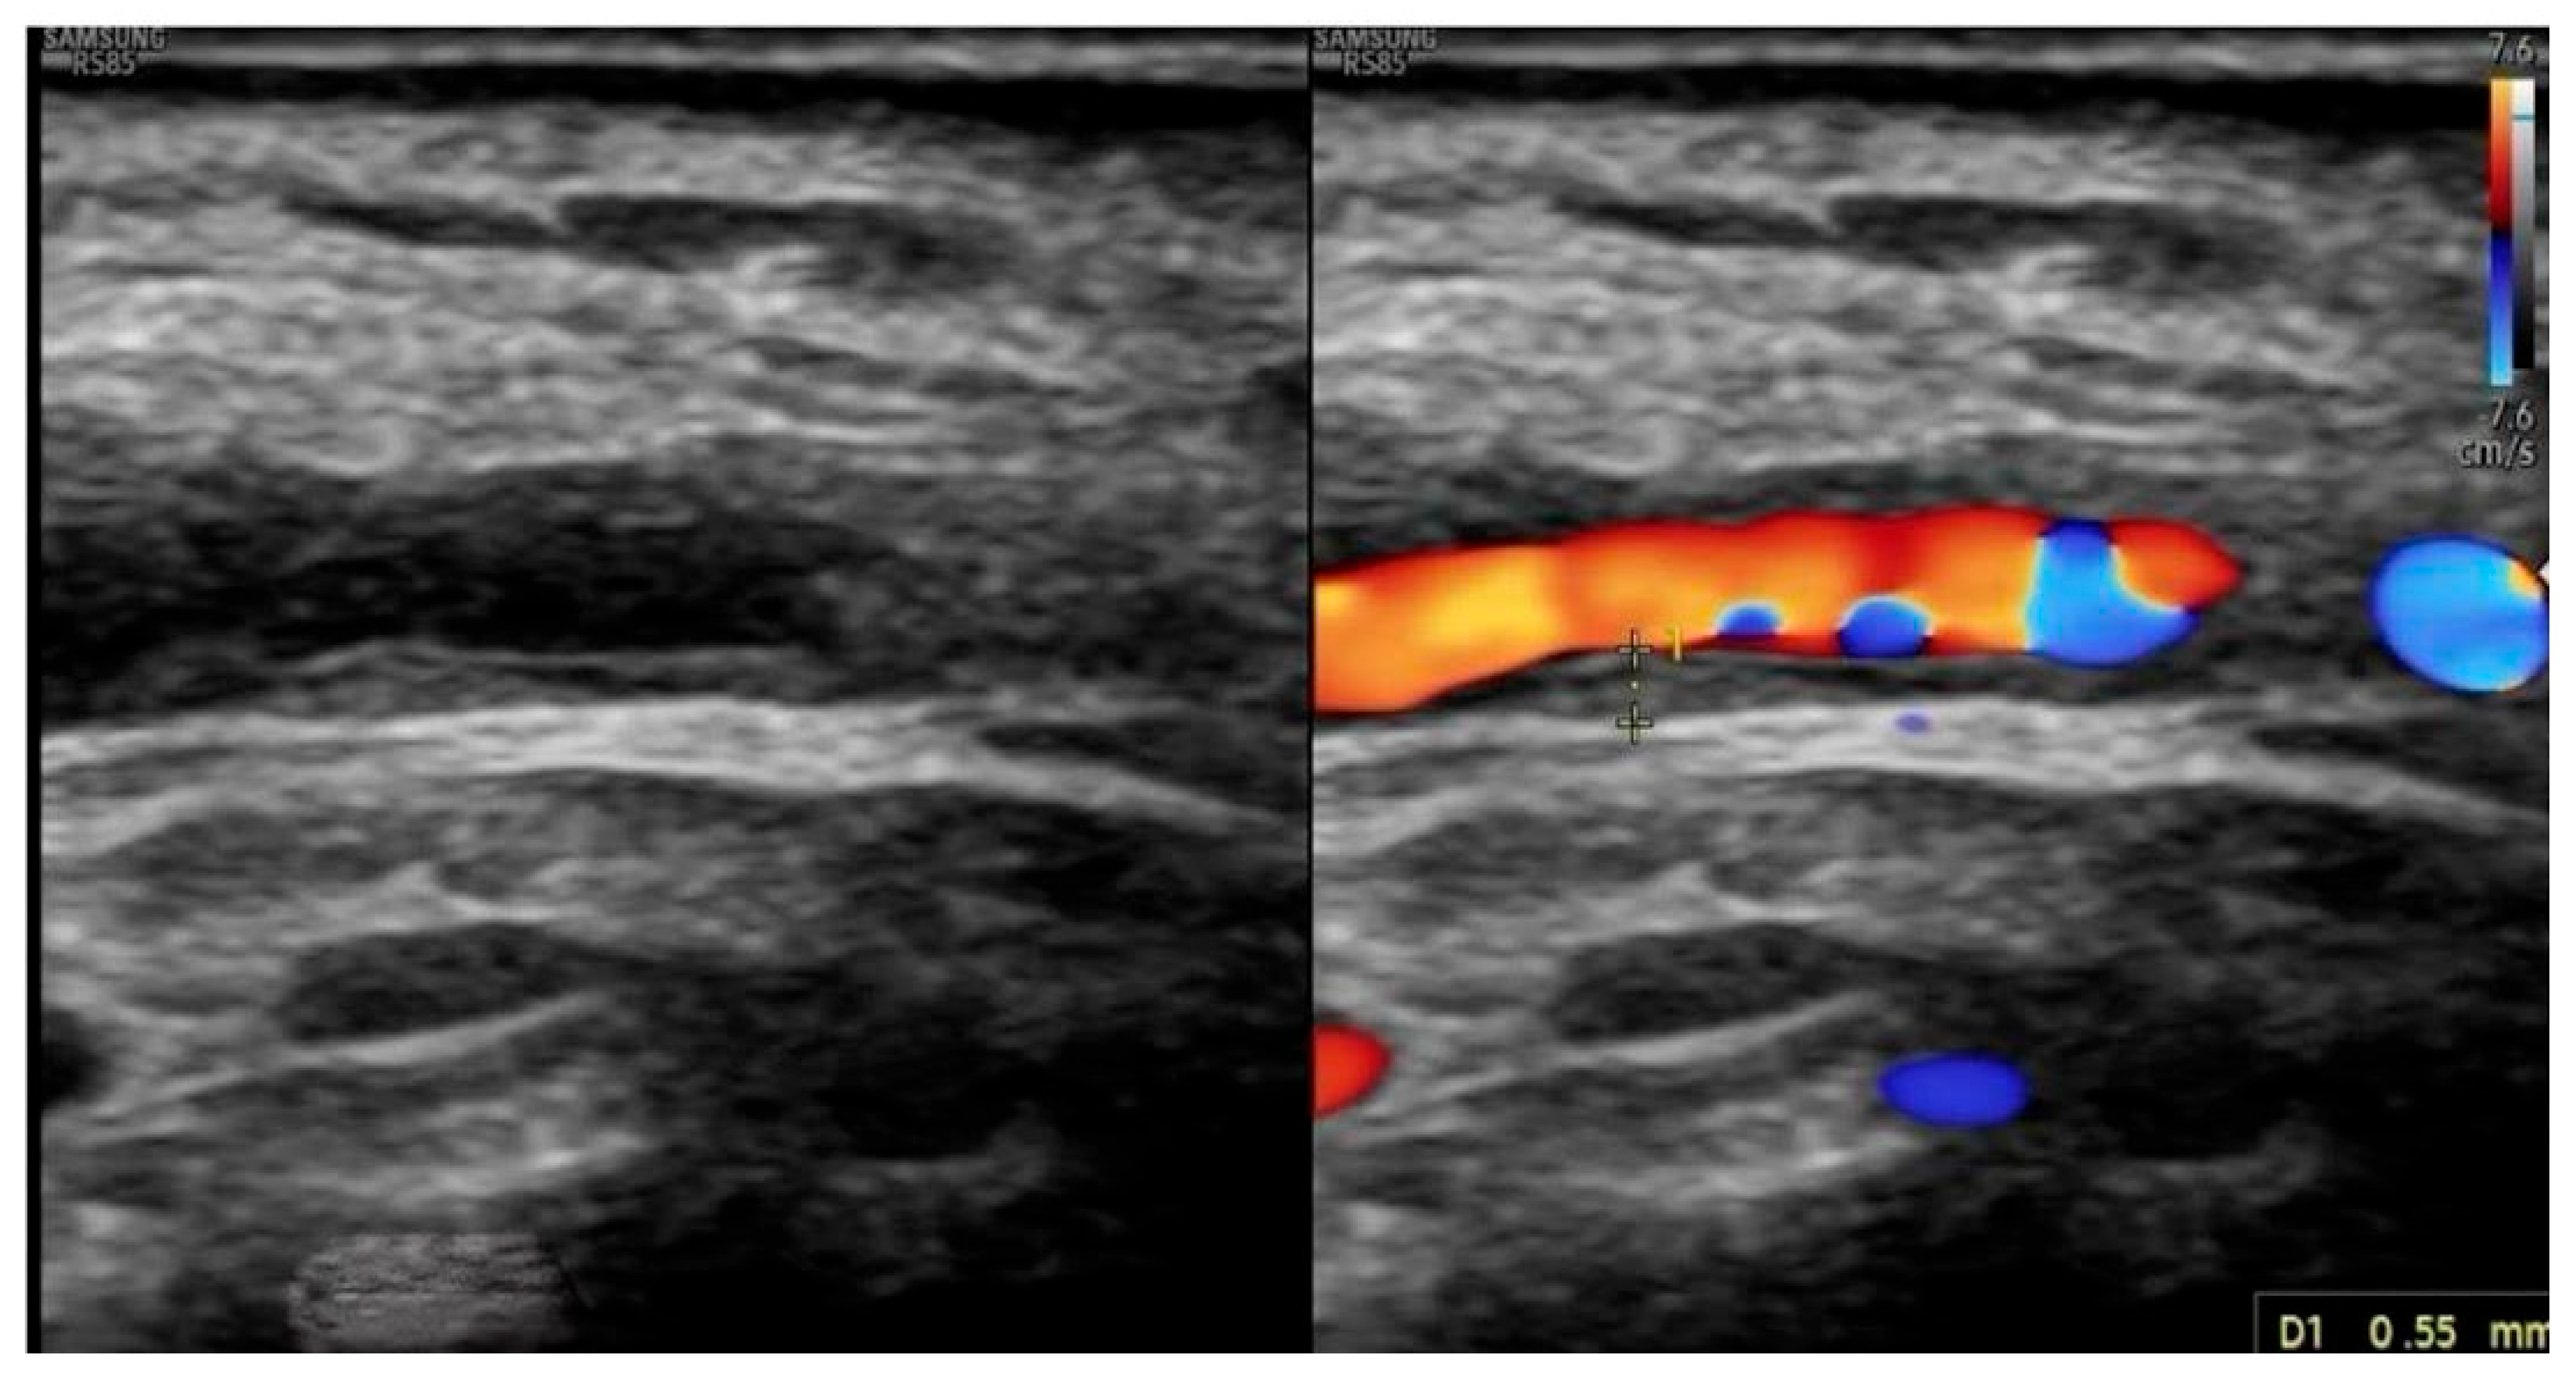

Extended Color Doppler Ultrasound in the Diagnosis of Giant Cell Arteritis: Clinical Insights and Literature Review with Emphasis on Posterior Circulation Involvement

- The use of extended CDUS protocols, including assessment of temporal, axillary, subclavian, carotid and vertebral arteries.